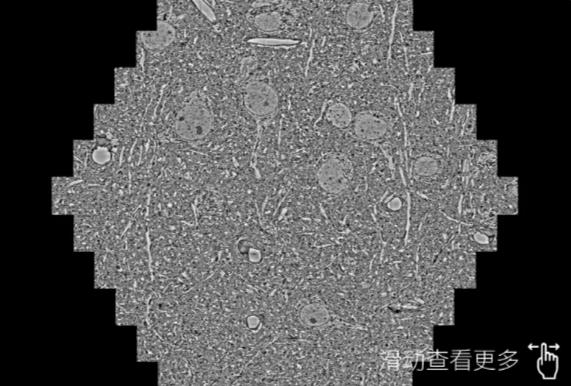

鼠脑切片。左图使用房山蔡司房山扫描电镜MultiSEM706对165μmx143pm面积区域成像,耗时仅需1.5秒。右图为鼠脑切片中30μm区域放大效果。样品由芝加哥大学B.Kasthuri提供。